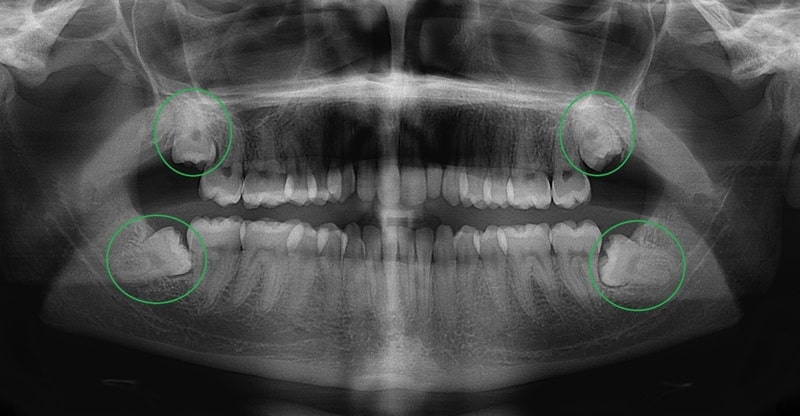

Nhổ răng khôn ở đâu tốt nhất, giá rẻ tại quận Đống Đa, Hà Nội?